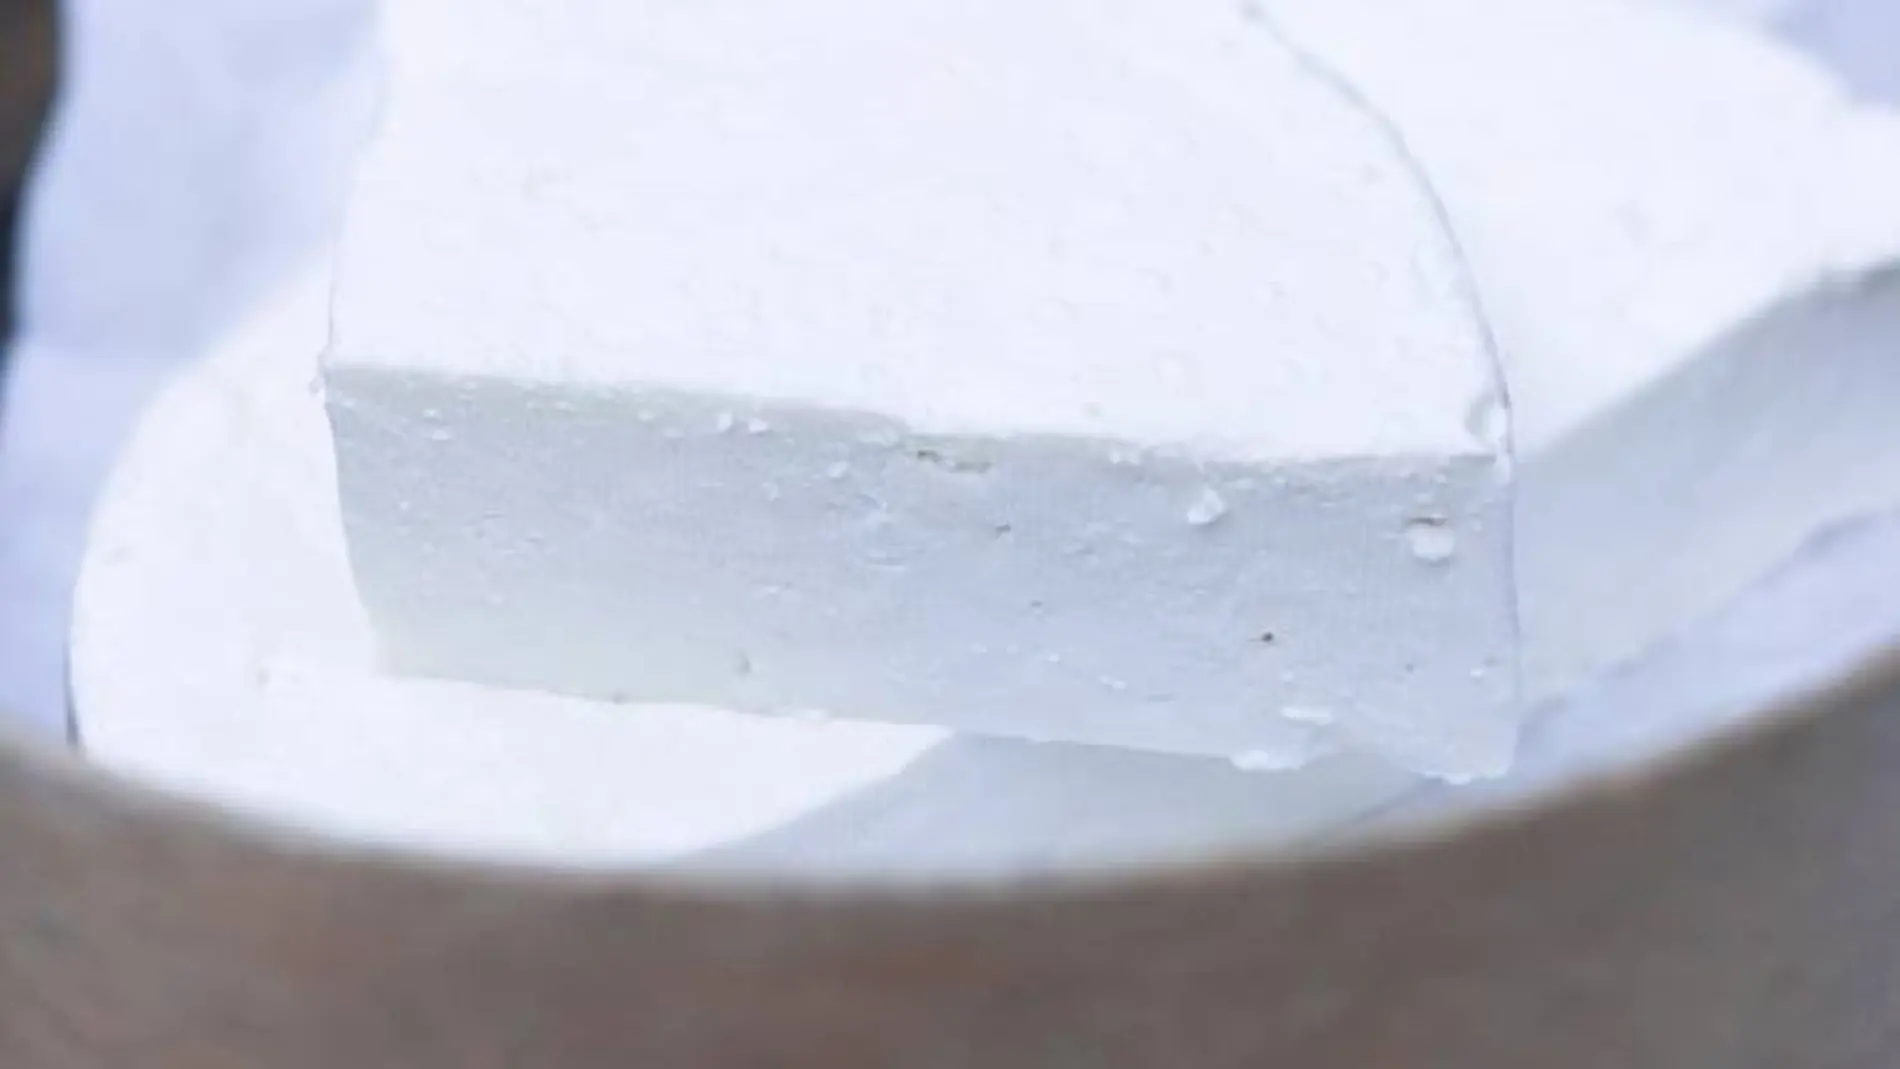

La normativa permite usar leche cruda en quesos frescos, de poca maduración, a diferencia de lo que sucedía antes, cuando era obligatorio en esos casos usar leche pasterizada. Por tanto, llegan al mercado quesos elaborados con leche cruda han tenido menos de 60 días de maduración, informa la Organización de Consumidores y Usuarios (OCU).

Durante el periodo de maduración el queso pierde humedad, se concentra la sal, se producen procesos de fermentación que liberan ácido láctico. En definitiva, la maduración es garantía de conservación de los quesos, ya que se crean condiciones que impiden el desarrollo de patógenos como la Salmonella, Escherichia coli o Listeria.

A juicio de OCU, es muy importante que las empresas que se dediquen a elaborar quesos con leche cruda sean extremadamente escrupulosos con la calidad del proceso en todos sus pasos, desde el propio ordeño, a la manipulación o el tratamiento en la quesería, pues se trata de productos que no llevan ningún proceso térmico (a diferencia de lo que sucede si se trabaja con la leche pasterizada) y todas las bacterias que pudiera haber en la leche pasan directamente al queso, con el consiguiente riesgo.